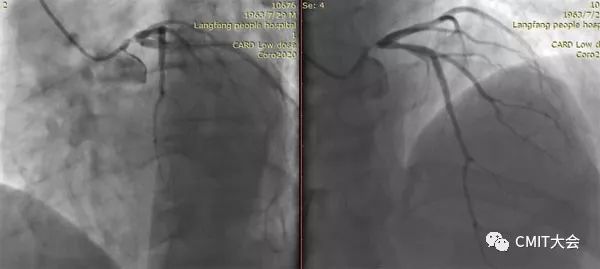

➢ CASE 1

➢ CASE 2

右冠起源异常,开口于左冠窦